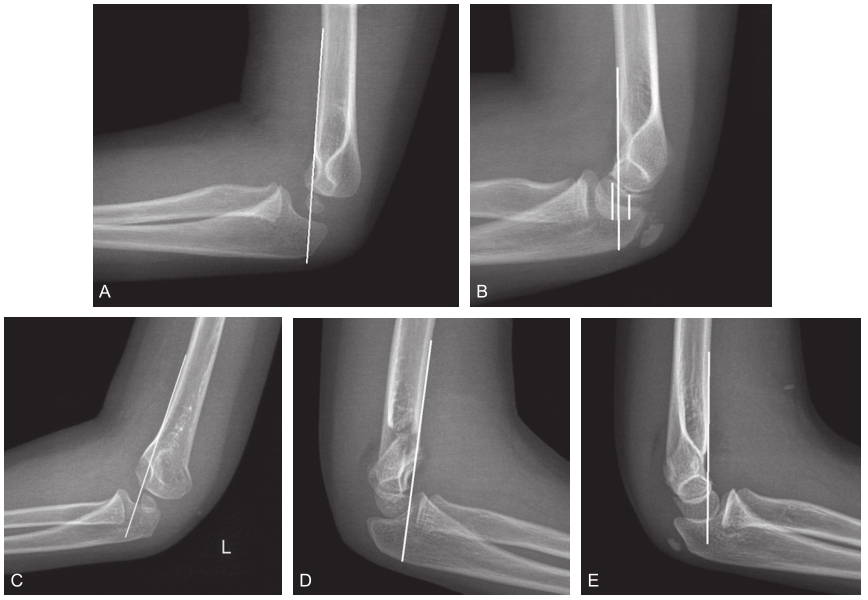

肱骨前倾角

夯实基础:肱骨髁上骨折之诊断篇

肱骨前皮质与肱骨外 髁骺轴线(肱骨小头 中心线)约成25度夹 角,另外

参考意义:肱骨远端存在40°的前倾角,同尺骨鹰嘴的倾斜角度一起,使

脂肪垫征,双弧征,肱骨前线,这三种肘部征象你了解吗?

一般来说:年龄越小的儿童,ahl越靠近肱骨小头的前方(前倾角的发育机制

4.肱骨干轴线与肱骨髁轴线之间有30°-50°的前倾角

临床必备:儿童肱骨髁上骨折,复位方法及经皮穿针技巧详解!